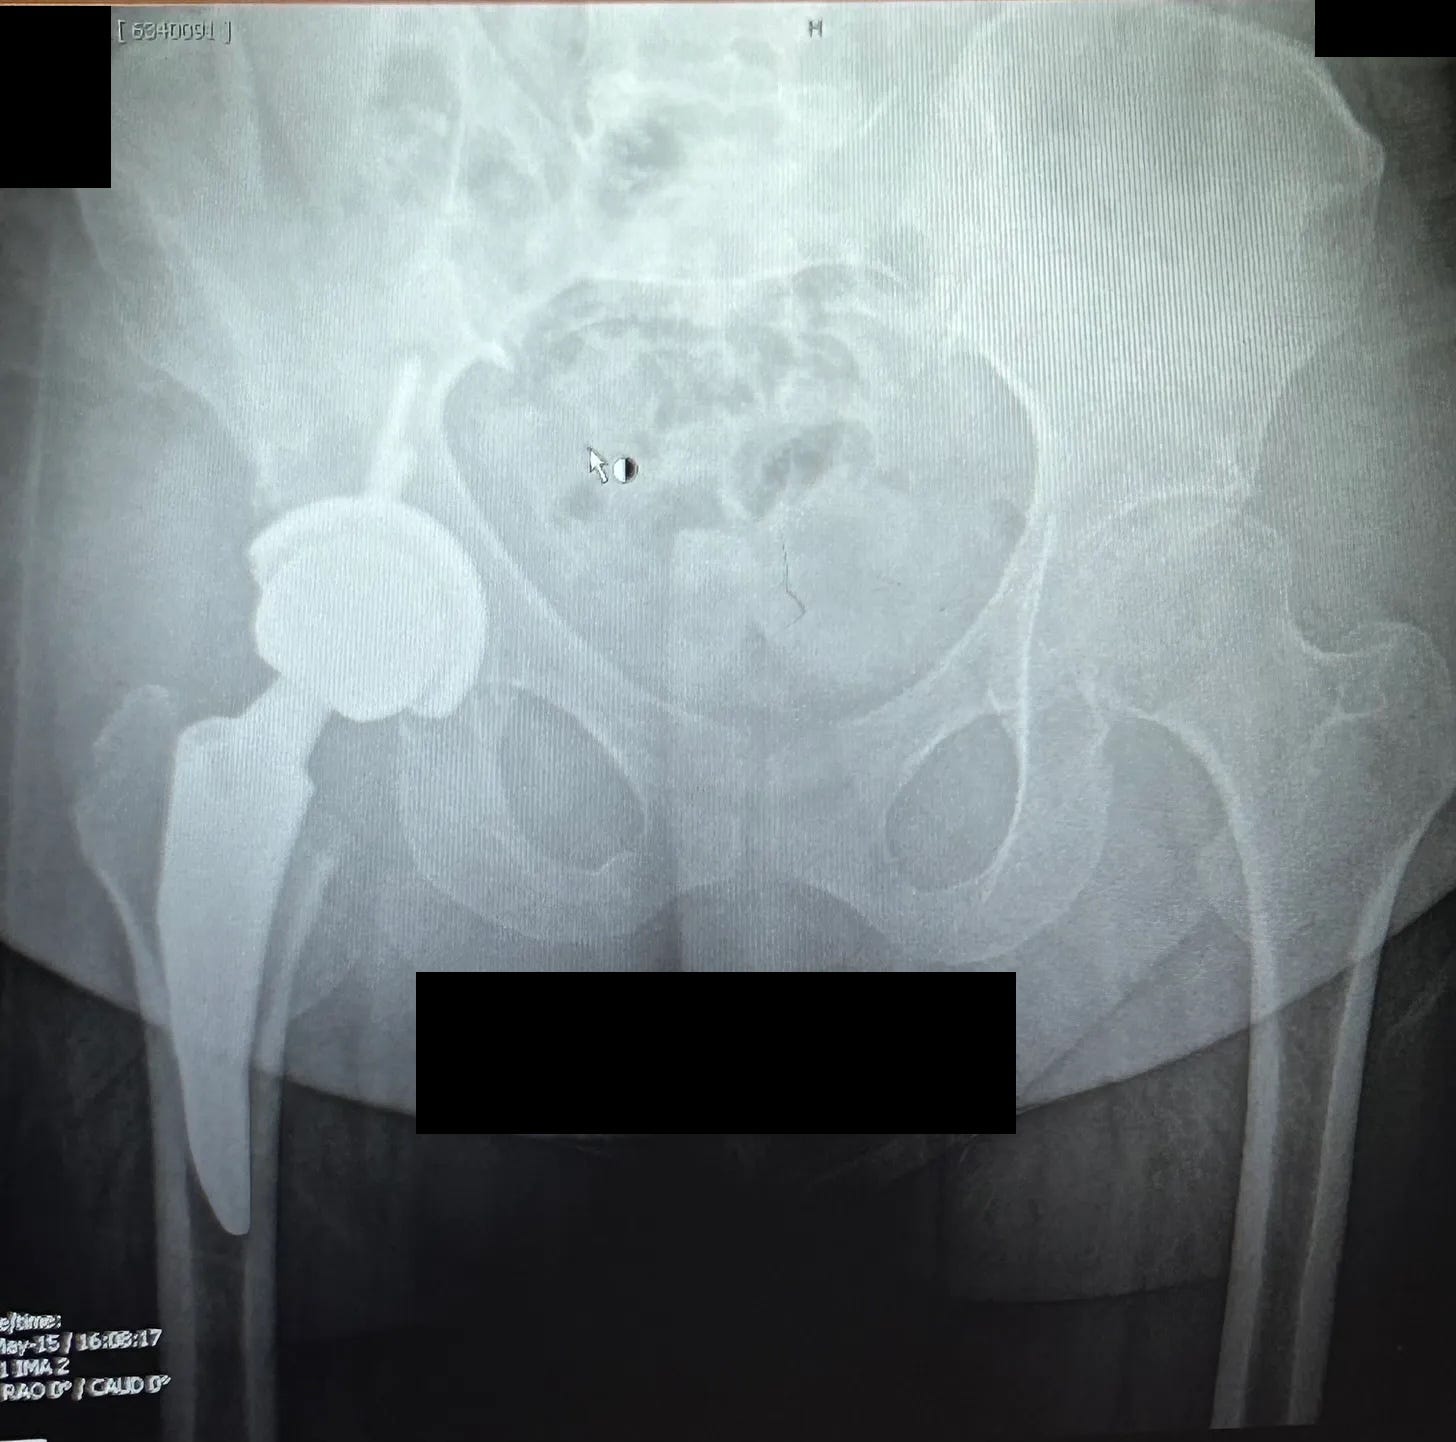

Six months post-op, I had an X-ray taken to check on my implant. The doctors wanted to see if it was still positioned correctly. It grossed me out to think about something inside me that could move out of place. Thankfully, they said it looked perfect — and hopefully it stays that way.